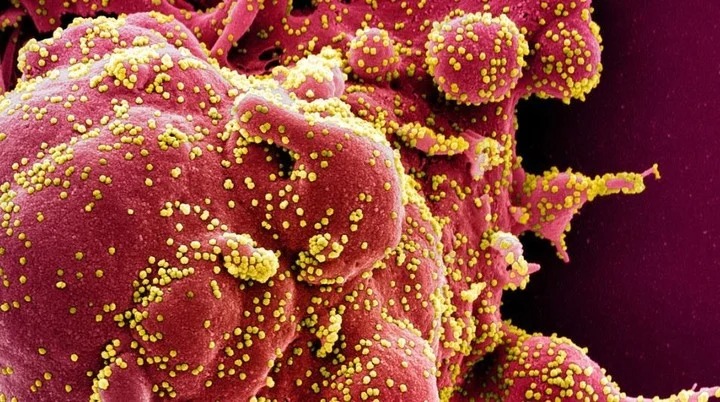

Es el S2H97, que podría ser la piedra fundacional de la madre de todas las vacunas contra el coronavirus.

La investigación científica sigue dando pasos agigantados en plena pandemia de coronavirus, y un último descubrimiento llena de esperanza a la comunidad científica internacional: se trata de un súper anticuerpo, el S2H97, que no solo sería eficaz contra muchas variantes del Sars-CoV-2 sino que también contra coronavirus estrechamente relacionados.

Este descubrimiento fue publicado en la revista Nature y sería clave para alcanzar una vacuna anti covid de alcance casi total. Uno de los autores del estudio, Tyler Starr, bioquímico del Centro de Investigación del Cáncer Fred Hutchinson, en Seattle, Estados Unidos, explicó que gracias a este super anticuerpo se solucionaría el problema de que alguna variante del Sars-CoV-2 haya mutado y se pueda escapar al efecto de los anticuerpos.

El S2H97 respondió bien ante las variantes británica (Alfa), la sudafricana (Beta), la brasileña o de Manaos (Gamma) y la india (Delta). El hallazgo se basa en trabajos realizados con hámsters y son aún incipientes, pero la esperanza en desarrollar esta vía ya está abierta.

Según el estudio de Nature, este anticuerpo no se puede probar contra virus desconocidos, pero sí permitirá avanzar en el desarrollo de vacunas. Sería algo así como la “madre de todas las vacunas” o una supervacuna. Los investigadores trabajaron con 12 anticuerpos distintos de personas que habían pasado la enfermedad y comparándolos, han hallado uno, el S2H97, que no permite ser superado por ninguna de las variantes del Sars-Cov-2 y otros coronavirus.

Los autores del estudio querían buscar una solución al problema que tienen algunos tratamientos actuales contra el Covid-19, y ese no es otro que las variantes, porque algunas de estas mutaciones permiten que el virus escape del alcance de los anticuerpos.

El S2H97 tiene la capacidad de adherirse a los dominios de unión de todos los sarbecovirus que probaron los investigadores y pudo evitar que una variedad de variantes del SARS-CoV-2 y otros sarbecovirus se propagaran entre las células que crecían en el laboratorio. También fue tan potente como para proteger a los hámsters contra la infección por SARS-CoV-2. “Ese es el anticuerpo más genial que descubrimos”, dijo Starr.

Un examen más preciso de la molecularidad del S2H97 reveló que se dirige a una región previamente invisible y bien oculta en el dominio de unión, una sección que se revela sólo cuando el dominio aparece para unirse al receptor de una célula. Starr dijo que las moléculas que se dirigen a esta región de dominio de unión podrían generar protección contra múltiples virus, y algún día podrían usarse en vacunas.